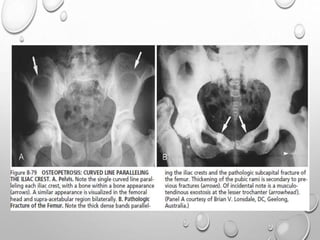

PELVIS – MULTIPLE DENSE CURVED LINES PARALLELING THE ILIAC

CREST